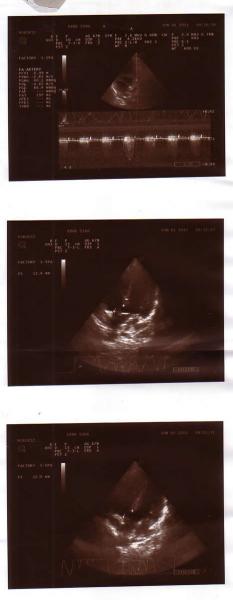

И сейчас мой 4-летний самый младший сынок Муборизи Гозибекпур очень болен: у него врожденный порок сердца. С самого начала нас убеждали, что это израстется, пройдет к трем годам, но оказалось он не числе тех счастливчиков, которых излечивает время. Ребенку срочно нужна операция.